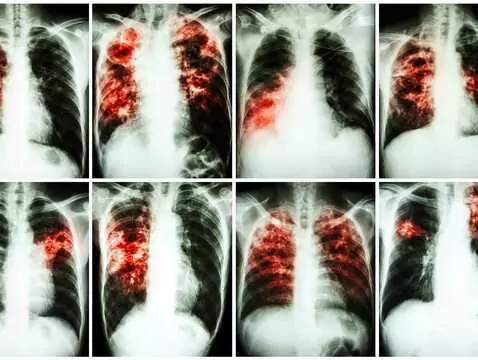

Tuberculosis - a disease that has not gone away. On World Tuberculosis Day, it is worth remembering the most important information about the disease.

There are diseases that are said to be 'extinct' or only appear in so-called Third World countries. One such disease was tuberculosis, considered to be a disease entity that appears sporadically in...

Researchers from the Hradec Králové medical faculty of Charles University in Prague have invented a new drug against tuberculosis. The drug has been sold to an American pharmaceutical company, which...